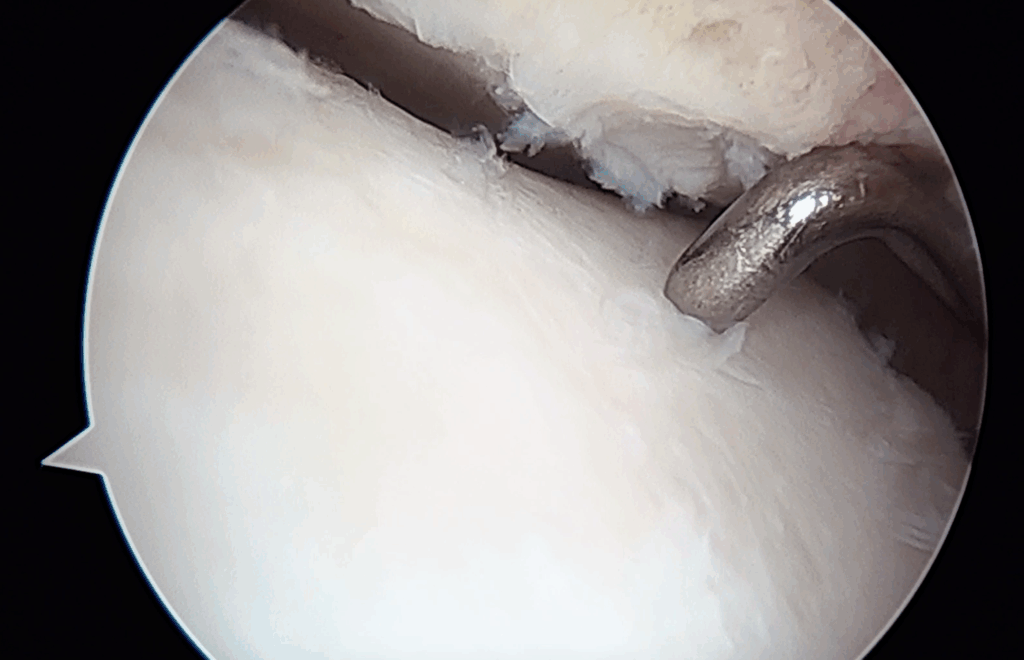

Particolarmente utile risulta essere nelle sindromi da “impingement”, ovvero in quelle situazioni in cui si crea un conflitto fibroso che rende doloroso e limitato il movimento. Questa situazione clinica è molto frequente negli esiti di fratture, soprattutto quelle trattate chirurgicamente in cui il danno articolare quasi sempre presente (fino all’80%) può evolvere in una vera e propria degenerazione artrosica di tutta l’articolazione.

Il danno cartilagineo quando ben limitato, può essere contenuto proprio grazie a procedure artroscopiche specifiche; anche in questo caso le opzioni terapeutiche, anche grazie alle nuove tecniche innovative proposte negli ultimi anni, sono molteplici e l’accurata selezione del paziente, con un dettagliato planning personalizzato ci permette di scegliere il miglior trattamento possibile.

In questi casi, nelle lesioni più piccole, è possibile rimuovere frammenti di cartilagine e stimolare il tessuto osseo spongioso con microperforazioni; in quelle superiore a 1,5 cm2 è possibile rimuovere frammenti cartilaginei, effettuare microfratture per stimolare la rigenerazione del tessuto osteo-cartilagineo. È possibile inoltre eseguire degli innesti di tessuto mesenchimale da tessuto adiposo o con matrice autologa, sempre per via artroscopica, con l’obiettivo di riempire la perdita di sostanza, ottenendo la risoluzione, o il miglioramento della sintomatologia e della funzionalità della caviglia.